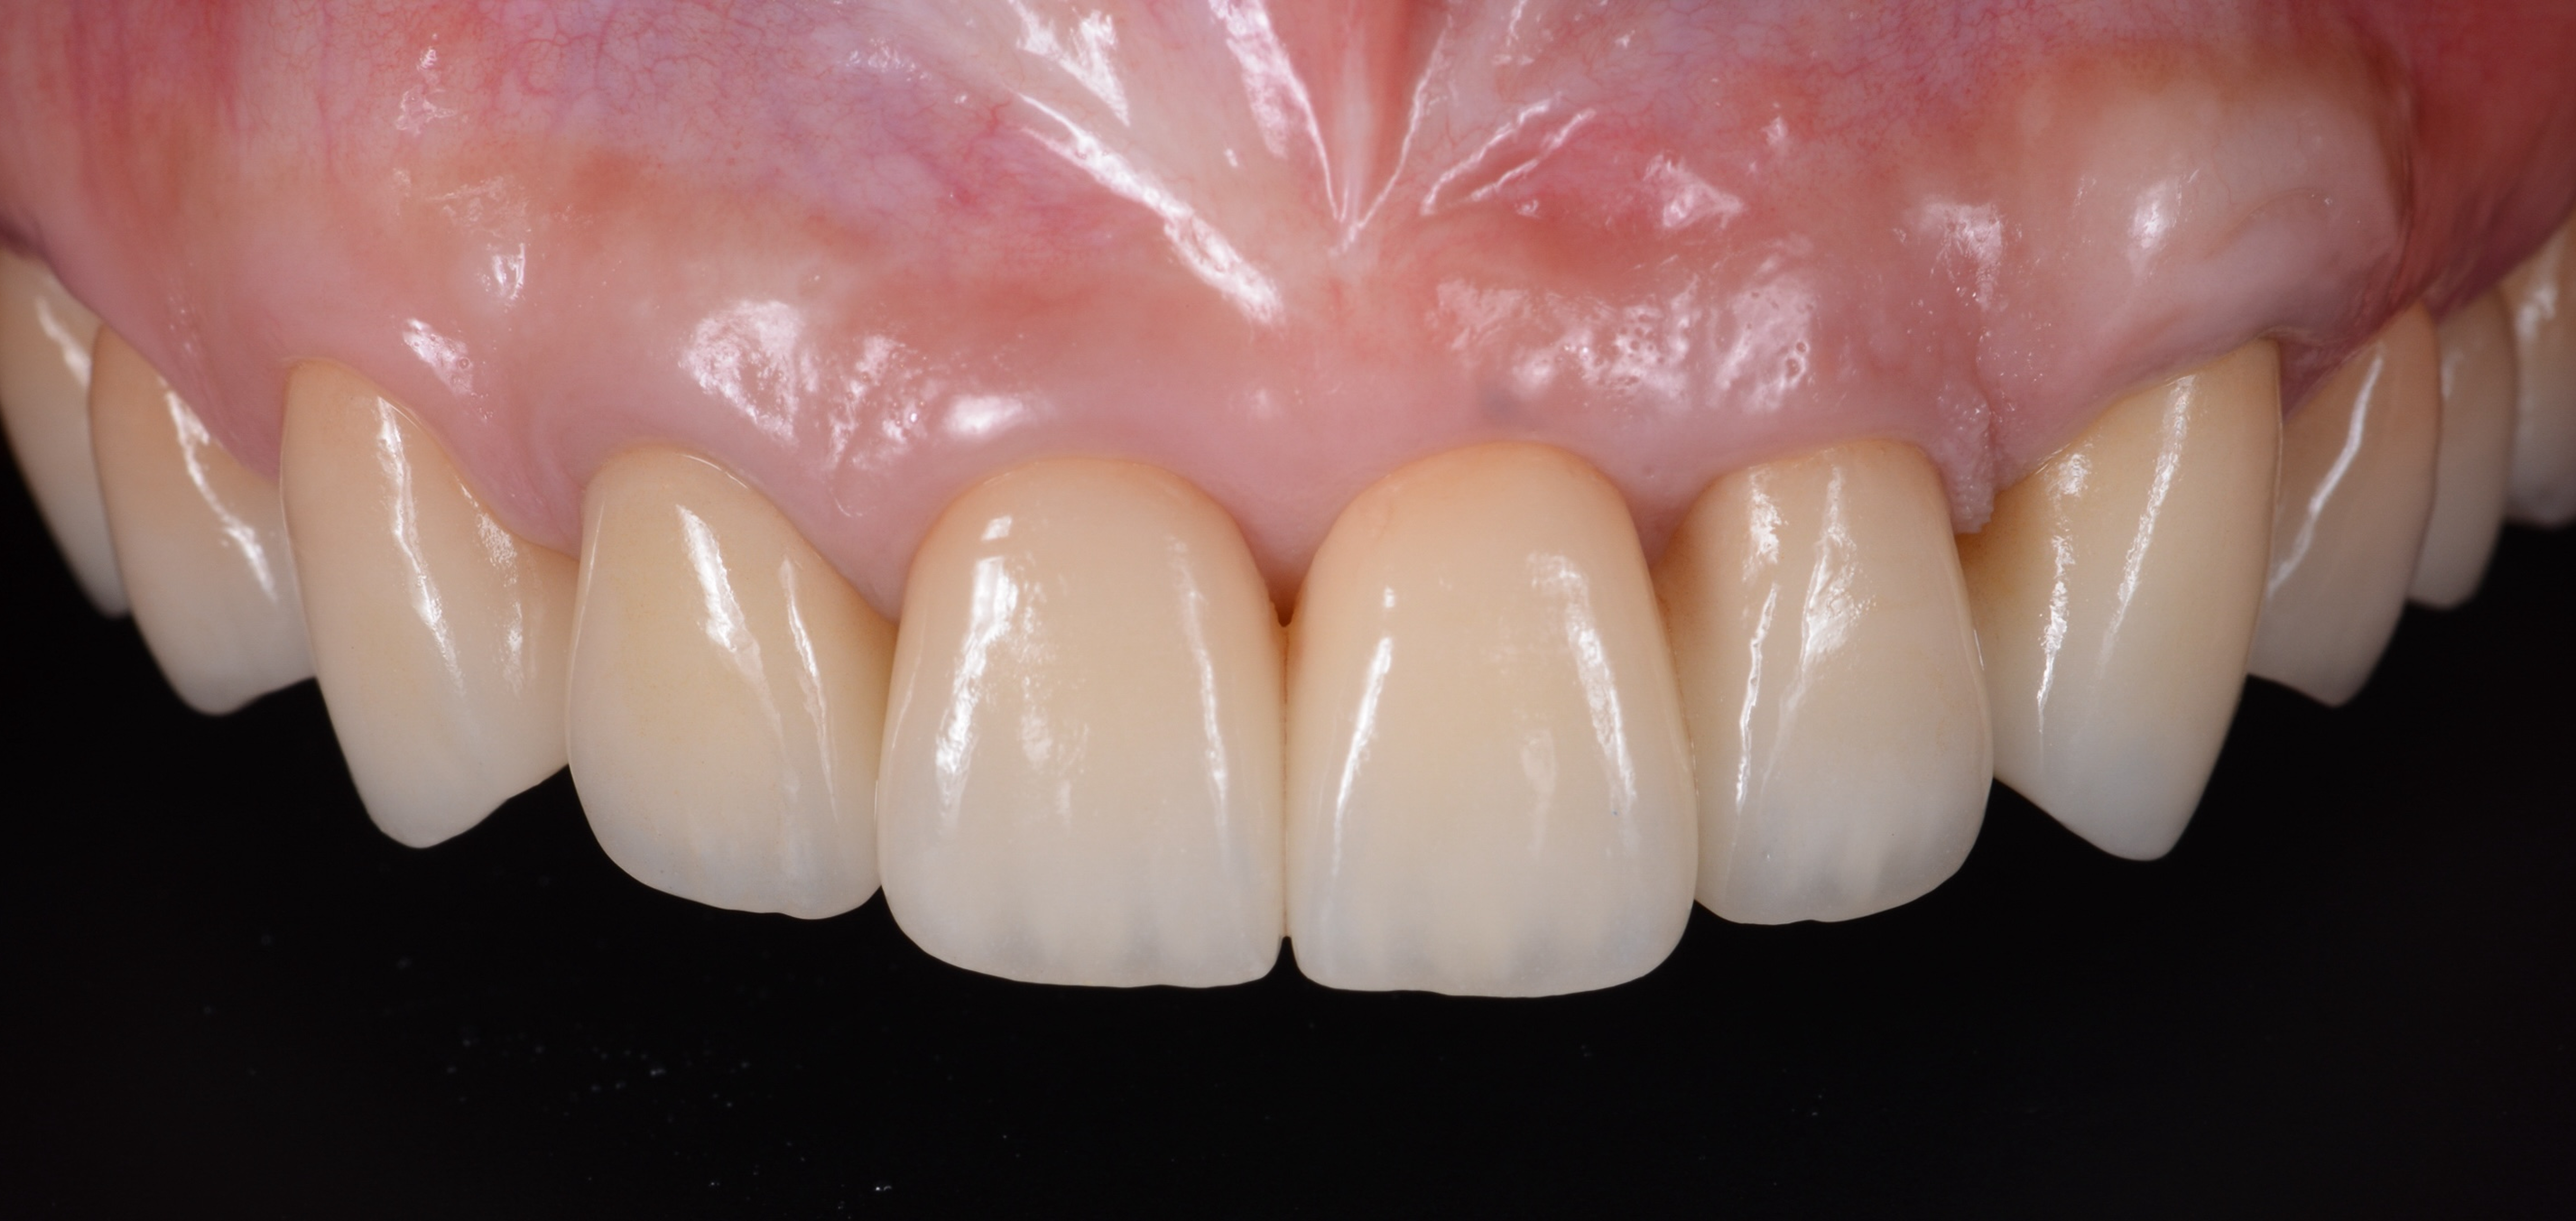

ガミースマイルを歯周形成外科で改善し、笑顔を取り戻した症例

- 年代、性別 30代・女性

- 来院動機 ガミースマイルを治したい

- 治療内容 歯周形成外科

ガミースマイルを歯周形成外科で改善した症例

- 年代、性別 27歳・女性